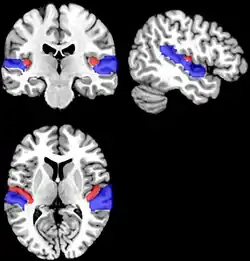

![]() Hemisferio cerebral izquierdo: localización del giro temporal superior. | ||

El giro temporal superior es una circunvolución del cerebro. Es la primera circunvolución del lóbulo temporal también llamada T1 abreviadamente. Constituye el labio inferior de la cisura de Silvio y se continúa hacia atrás con el giro supramarginal.[1] Contiene la corteza auditiva y su lesión determina el trastorno llamado afasia de Wernicke.

Anatomía

El lóbulo temporal superior presenta una porción silviana y otra lateral extra-silviana.[4][5]

La porción intra-silviana corresponde a la superficie del plano temporal superior.

Allí se encuentran los giros temporales transversos anterior y posterior (o de Heschl), que solamente en uno a dos tercios del sector medial de estos giros, albergan la corteza auditiva primaria y que se corresponden con las áreas 41 y 42 de Brodmann.

La porción extra-silviana lateral del giro temporal superior, en sus dos tercios laterales y caudales alberga el área 22, conocida como área de Wernicke.